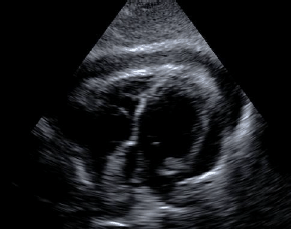

Um paciente de 29 anos foi vítima de ferimento por arma de fogo no 5º espaço intercostal esquerdo, na topografia da linha hemiclavicular, e chega ao Centro de Trauma. Apresenta-se agitado, sudoreico e com pulsos filiformes. O paciente é submetido a um e-FAST (extended-FAST) e identifica-se a imagem abaixo. Qual a conduta mais apropriada para esse caso?